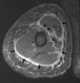

Fasciitis

Plantar fasciitis is a disorder of the connective tissue which supports the arch of the foot. It results in pain in the heel and bottom of the foot that is usually most severe with the first steps of the day or following a period of rest. [Source: Wikipedia ]